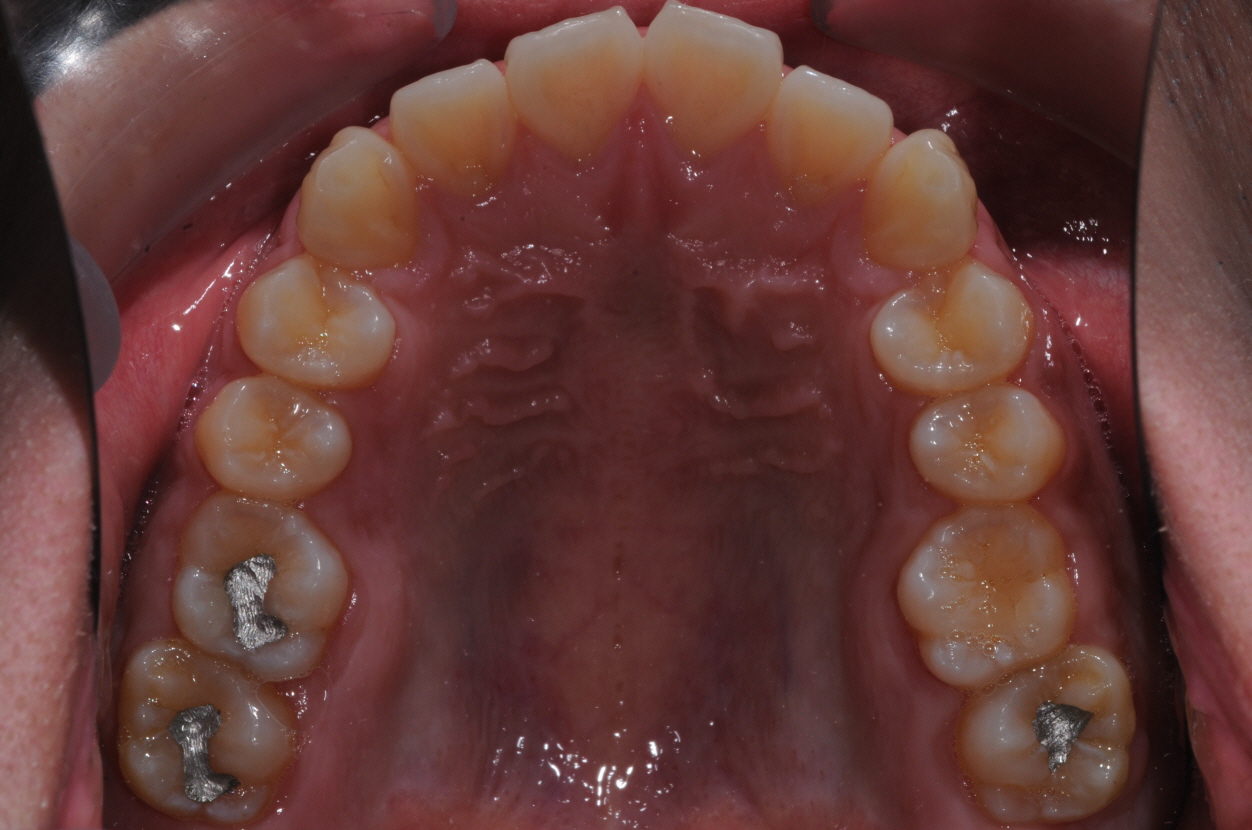

네... 사진 잘 보았습니다. 고민이 많이 되겠군요. 님의 상태는 일반적인 돌출입 부정교합이라고 판단이 됩니다. 그리 어려운 요소도 없구요. 일반적인 브라켓 교정치료로 진행하여도 1년반에서 2년 사이정도에서 교정이 이뤄지리라 예상이 됩니다. 님이 문의하신 교정법들은 치아의 이동을 좀더 빠르게 하는 조치들 인데요. 대략 6개월정도의 단축 효과정도 있으리라 생각이 됩니다. 즉, 1년 남짓정도는 걸리게 되지요. 1번과 3번의 치료방법은 수술의 심적인 부담이 많은 편이랍니다. 2번의 치료는 돌출된 입의 선행적인 치료가 장점이고 치료기간의 메리트는 그리 없지요. 저의 경우는 킬본 교정이라는 장치를 사용하여 2번의 방식데로 치료를 하는 경우가 많이 있는데 주 목적은 치료기간의 단축에 있는 것이 아니라 잇몸돌출의 해소와 앞서 언급한 돌출의 선행적인 해소에 있답니다. 4번의 방법은 님이 진동기를 일정시간 물고 있는 것인데 저는 사용을 하지 않아 뭐라 말씀을 드리기가 그렇습니다. 어쨋든 1번부터 4번까지의 치료는 특별한 부작용이 있는 치료들은 아니랍니다. 님이 언급한 교정치료 중의 애로사항인 심미적인 부분은 장치의 위치를 안으로하는 방법등을 고려해 볼 수 있구요. 발음은 교정치료 후 3개월 정도 되면 대부분 적응을 하는 것 같습니다. 참고가 되셨는지 모르겠네요...^^